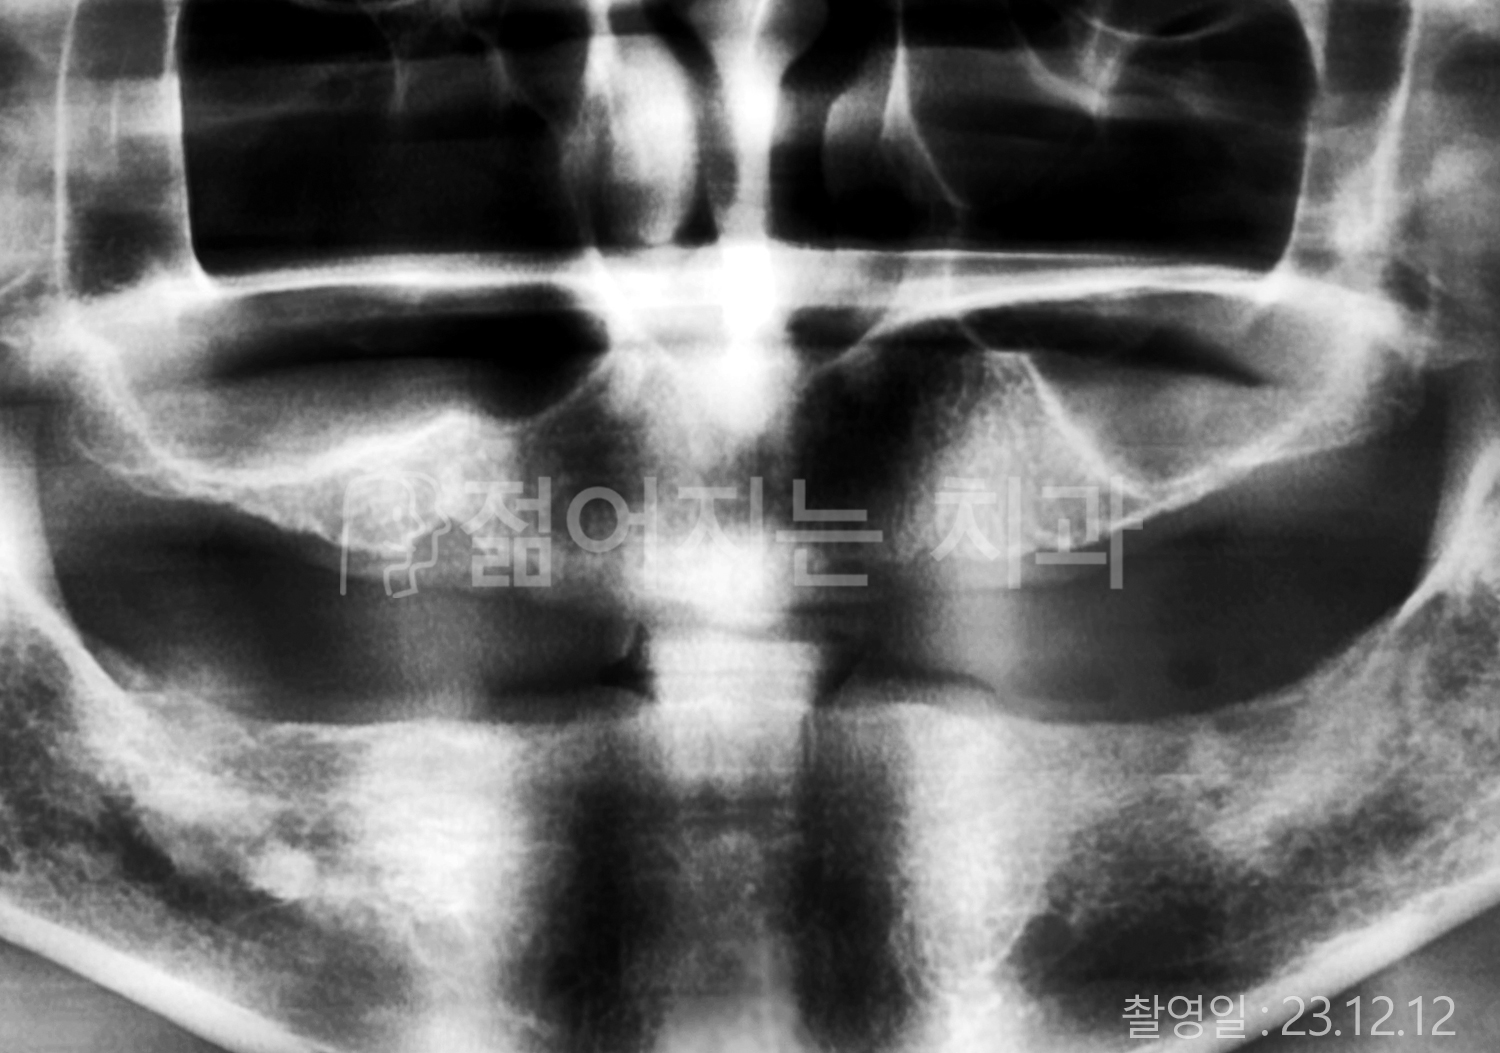

• 50대 전체치아 10개 이상 임플란트